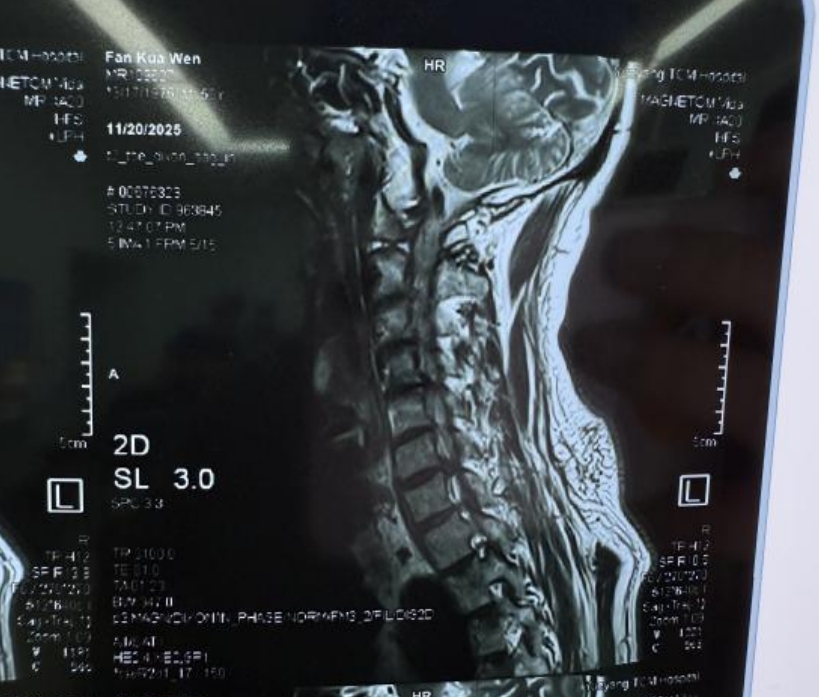

患者为50岁男性,曾于去年在岳阳市中医医院因腰椎间盘突出接受微创手术,疗效显著,左侧腰腿部疼痛完全消失。今年,他因持续加重的颈肩部疼痛并伴有右上肢放射痛和麻木,再次来到医院求诊。经详细检查,被明确诊断为“神经根型颈椎病”,病变位于颈4/5和颈6/7节段。

结合患者病情,考虑他期望快速康复、保留颈椎功能的诉求,岳阳市中医医院脊柱骨科主任刘建国和管床医生易生辉带领团队经过周密术前讨论,决定为其施行目前国内领先的“大通道脊柱内镜下右侧颈4/5、颈6/7椎间盘突出髓核摘除+脊髓神经根粘连松解+射频消融术”。